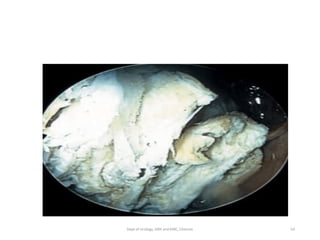

• Cystoscopy: Exophytic,

• sessile mass

• Grape like,

• Papillary lesions

• fulgrated area

136